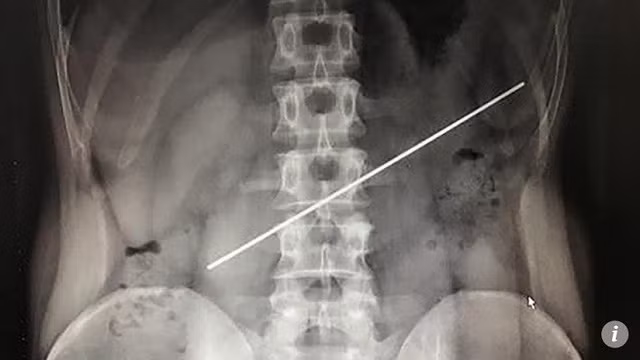

Người đàn ông không cảm thấy đau đớn nhưng một năm sau mới, đến bệnh viện để kiểm tra. Ảnh chụp X-quang cho thấy phần cuối thanh thép đâm thủng dạ dày.